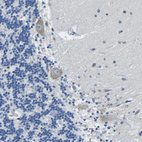

Immunohistochemical staining of human cerebral cortex shows moderate cytoplasmic positivity in neuronal cells.